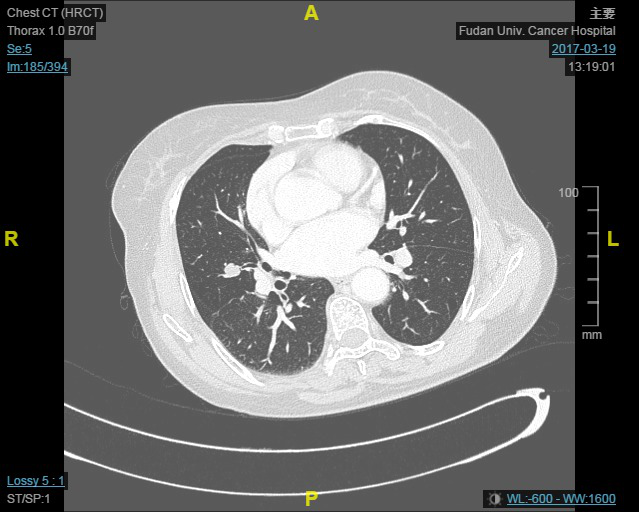

女, 60岁, 行胸部CT示右肺中叶类圆形肿块,大小1.4*1.2cm。2017年3月于我院行右肺中叶切除术及肺门淋巴结清扫。

巨检:送检右肺中叶,肺叶组织大小13.5*8.0*3.0cm,距支气管切缘1.5cm见一结节,大小1.3*1.2*1.1cm,质中界清,距胸膜0.2cm。